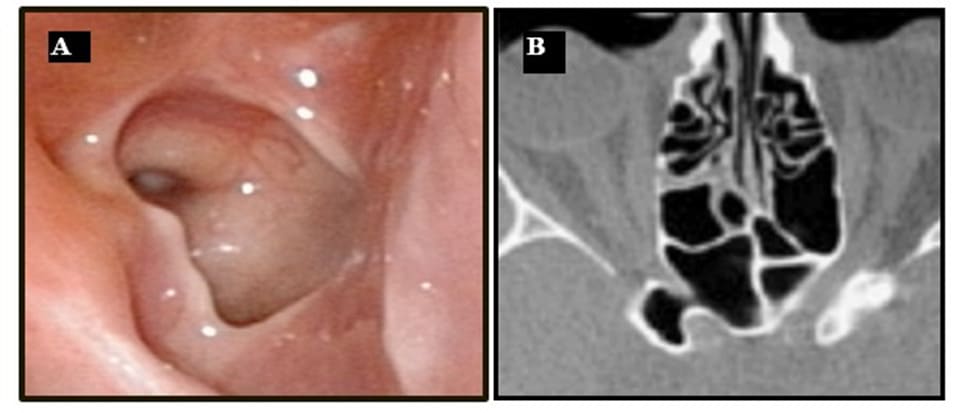

The lateral sinus wall contains noble structures. Often, the internal carotid artery (ICA) and the optic nerve (ON) can be identified bulging in the sphenoid cavity. In between there is the optico-carotid recess (OCR). In some cases, the maxillary nerve or the second branch of the trigeminal nerve (V2) and the Vidian nerve (V) may be recognized. The more pneumatized the sphenoid sinus, the more these structures are protruding. Therefore, they may be at risk during surgery, in case the surgeon is too posterior and lateral in the sphenoid cavity (3,12).

Figure 6: (A) Endoscopic view of the lateral wall with protrusion of the ICA and of the optic nerve. (B) Axial CT-scan showing the optic nerve in the sphenoid cavity.